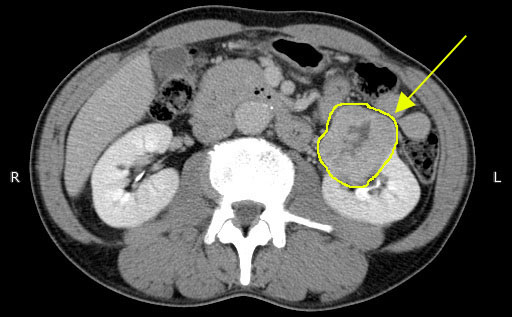

② CT検査

腎細胞がんの診断でもっとも大事な検査です。造影剤を使用して撮影する事により腫瘍の性状の判定に役立ちます。同時に転移や静脈内に伸びた腫瘍塞栓の有無を診断できます。

腎細胞がんCT

※腎細胞がんのCT画像